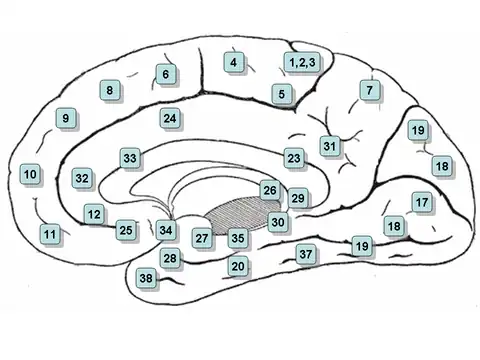

Medial surface. (Areas 23 and 31 at center right.) | |

Cytoarchitectonically the posterior cingulate cortex is associated with Brodmann areas 23 and 31.

The posterior cingulate cortex lies behind the anterior cingulate cortex, forming a part of the posteromedial cortex, along with the retrosplenial cortex (Brodmann areas 29 and 30) and precuneus (located posterior and superior to the PCC). The PCC, together with the retrosplenial cortex, forms the retrosplenial gyrus. The posterior cingulate cortex is bordered by the following brain regions: the marginal ramus of the cingulate sulcus (superiorly), the corpus callosum (inferiorly), the parieto-occipital sulcus (posteriorly), and Brodmann area 24 (anteriorly).[4]

The posterior cingulate cortex is considered a paralimbic cortical structure, consisting of Brodmann areas 23 and 31. As part of the paralimbic cortex, it has fewer than six layers, placing its cell architecture in between the six-layered neocortex and the more primitive allocortex of core limbic structures. It has also been associated with the hippocampocentric subdivision of the paralimbic zone. The cytoarchitecture of the PCC is not entirely uniform, instead it contains distinct anterior and dorsal subregions, which are increasingly understood as distinct in function, as well as cytoarchitectural structure.[4]